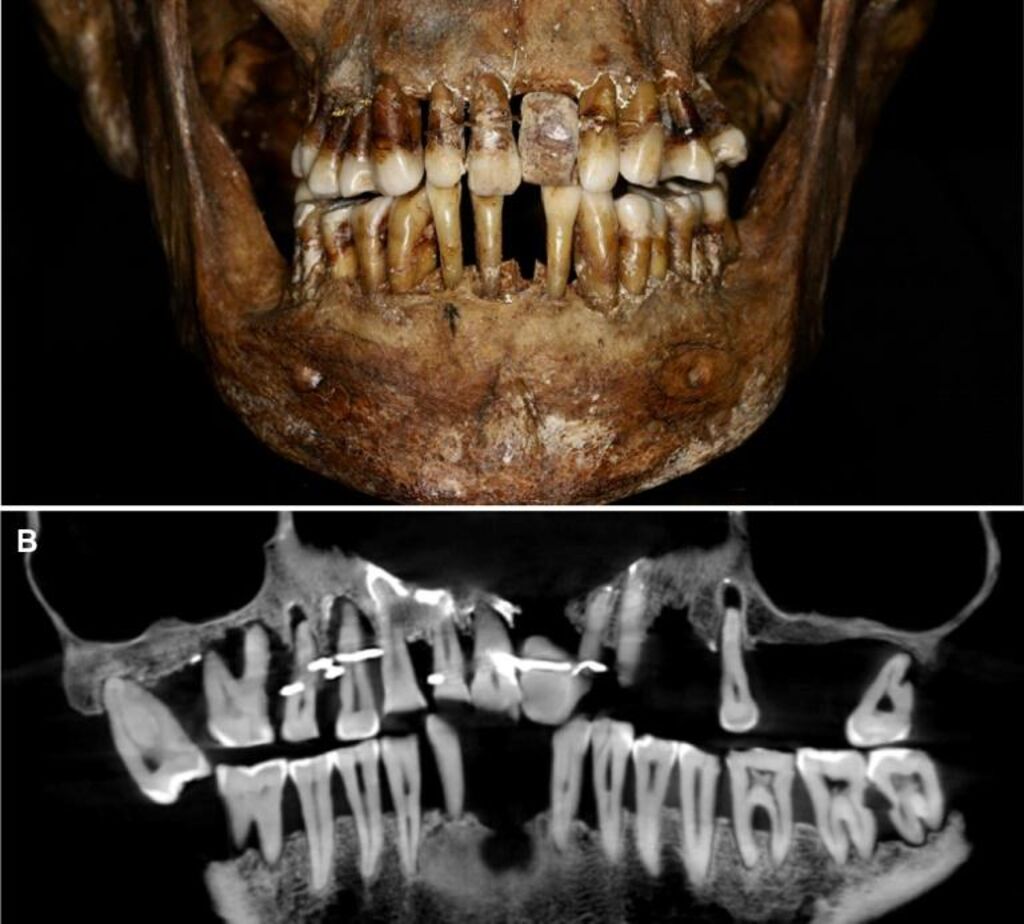

| Photo fournie par l'Inrap de la dentition d'Anne d'Alègre, une artistocrate du XVIIe siècle. |

La sépulture d'Anne d'Alègre, morte en 1619 à l'âge de 54 ans, avait été déterrée lors d'une fouille au château de Laval, en 1988. Embaumé dans un cercueil de plomb, le squelette était particulièrement bien conservé, sa dentition aussi.

Les archéologues avaient alors remarqué la présence d'une prothèse dentaire, mais ne disposaient pas d'outils d'analyse performants pour creuser plus avant.

Plus de trente ans après, une équipe comprenant des archéologues et des dentistes dévoile qu'Anne d'Alègre était atteinte d'une maladie parodontale qui provoque le déchaussement progressif des dents, selon une étude parue cette semaine dans Journal of Archeological Science.

Les images radiologiques par "Cone Beam", un scanner en 3D, montrent que la patiente portait une prothèse dentaire remplaçant une incisive, soutenue par des fils d'or, ainsi qu'une ligature de contention sur des pré-molaires. Des examens en macroscopie ont déterminé que cette prothèse était en ivoire d'éléphant, écartant la piste de l'ivoire de dents d'hippopotame, également utilisé à l'époque.